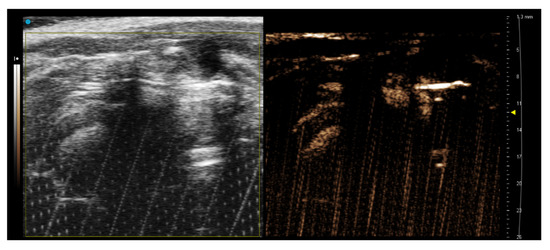

3.3. Hematoxylin/Eosin Staining–Histological Examination